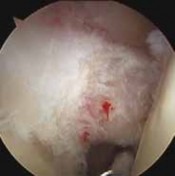

TECHNIQUES A B TECH FIG 2• Arthroscopic images showing intra-articular tenodesis of the long head of the biceps tendon at the proximal aspect of the bicipital groove. A. Anchor placement. B. Suture C D passage. C. Knot tying. D. Completed tenodesis. SOFT TISSUE TENODESIS Arthroscopic Fixation 1. This technique, in which the biceps tendon is secured to the soft tissues in the rotator interval, is based on the percutaneous intra-articular transtendon (PITT) technique described by Sekiya30 and Rodosky10 (TECH FIG 3).